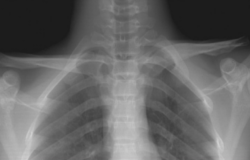

рентгенография – показывает сужение щели между дистальным отделом лопатки и ключицей;

2. Рентгенография при травме грудино-ключичного сустава:

• Часто без видимых изменений:

о Нормальные грудино-ключичные суставы могут быть приняты за суставы с подвывихом на рентгенограммах вследствие косого угла сустава

о Наложение грудных структур затеняет сустав

• Стандартные: передне-задняя, косая, боковая проекции грудино-ключичных суставов:

о Передне-задняя: вывих в случае разницы в краниокаудальных положениях медиальных концов ключицы >50% ширины головки ключицы

• Специальные проекции:

о Позиция по Роквуду («удачная»): луч направлен в сторону головы через рукоятку грудины у пациента в положении лежа на спине:

— Передний вывих: медиальный конец ключицы над горизонтальной плоскостью

— Задний вывих: медиальный конец ключицы ниже горизонтальной плоскости

о Проекция Хоббса: пациент сидит, наклоняясь над столом, а луч проходит через шейный отдел позвоночника:

— Усредняет 90° боковую проекцию грудино-ключичного сочленения

• Истинное неправильное положение грудино-ключичного сустава выявляется в 89% случаев при УЗИ в сравнении с 13% при рентгенографии